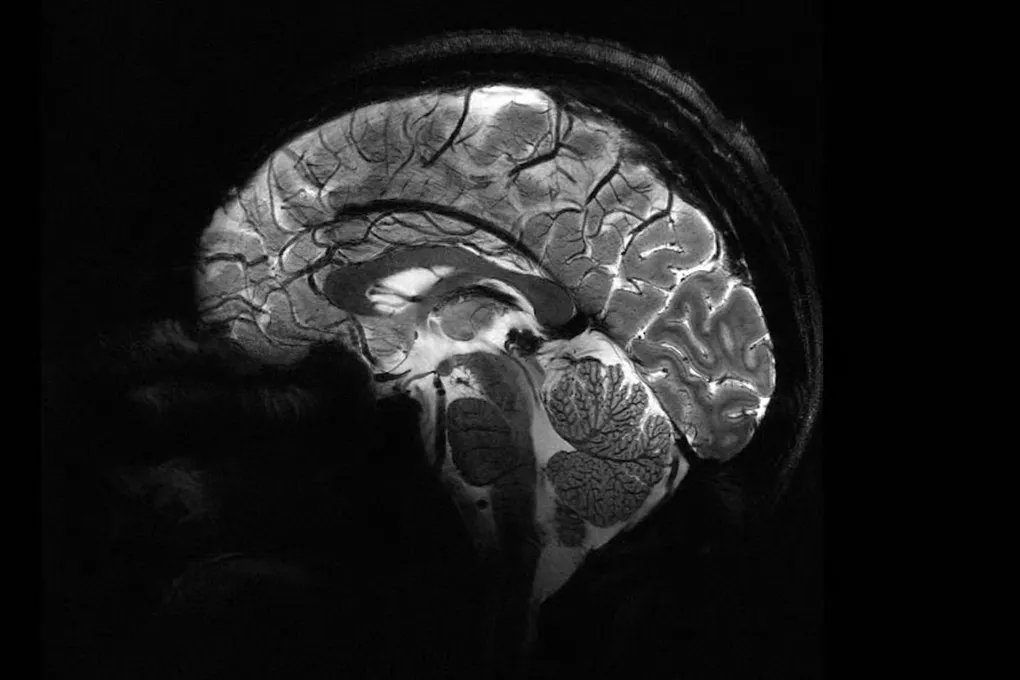

Представьте, что вы можете разглядеть мозг с такой детализацией, будто изучаете карту города с высоты птичьего полёта. Это стало реальностью. Самый мощный в мире МРТ-сканер, Iseult, наконец-то заглянул в человеческий мозг. Полученные изображения — не просто красивые картинки. Это окно в будущее нейронауки, где мы сможем расшифровать тайны сознания и найти ключи к лечению болезней Альцгеймера и Паркинсона.

Что это даёт? Фантастическую чёткость и скорость. Всего за четыре минуты Iseult делает снимки с разрешением до 0,2 мм по горизонтали, срезая слои толщиной в 1 миллиметр. На таком «срезе» умещаются тысячи нейронов одновременно. Удивительно, сколько информации можно собрать за время, пока вы завариваете чай, не правда ли?

Сначала были тыквы. Да-да, несколько лет назад гигант тестировали на овощах. Но теперь его «пациентами» стали 20 здоровых добровольцев. Результат? Снимки, от которых захватывает дух. Они открывают нам детали, которые раньше были скрыты: как мозг кодирует мысли, какие нейронные «подписи» соответствуют самому феномену сознания. Мы стоим на пороге величайшей загадки — и у нас появился инструмент, чтобы её разгадать.